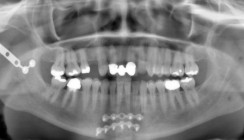

Resultate

Folgende gespaltene Zähne wurden restauriert und sind noch schmerzfrei intakt: 1 (2010), 2 (2013), 7 (2014). Mit der beschriebenen Technik scheinen laterale Frakturen ausnahmslos zu gelingen, zentrale Brüche nur, wenn der Furkationsraum keinen oder wenig Zahnstein enthält, und bei den apikalen Frakturen muss das langfristige Resultat erst noch abgewartet werden.